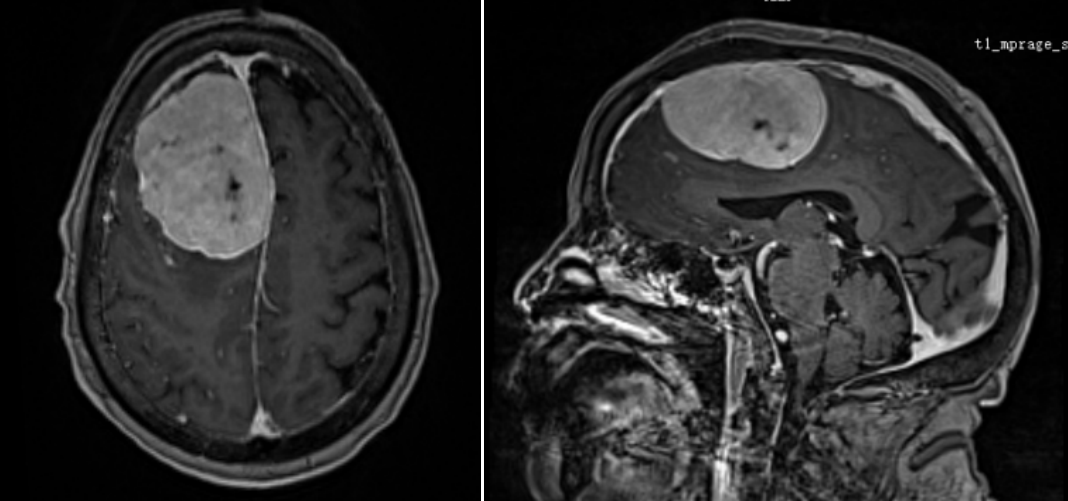

患者颅内肿瘤影像

时间回溯到年前,李奶奶被查出颅内肿瘤,且肿瘤已侵犯矢状窦、颅骨及头皮。由于年事已高,又身患多种慢性病,家属带着她辗转北京、上海多家医院求医,却均因手术风险过高被婉拒——多家医院认为,老人高龄叠加多重基础病,且长期使用抗凝药物,手术及麻醉过程中随时可能出现致命并发症,手术难度与风险远超常规。

一个月前,李奶奶病情突然恶化,出现严重食欲减退、意识模糊等症状,家属抱着最后一丝希望,将她送到湖南省第二人民医院脑血管神经外科就诊。入院检查显示,老人右额窦旁的巨大脑膜瘤已严重挤压脑组织,生命体征极不稳定。